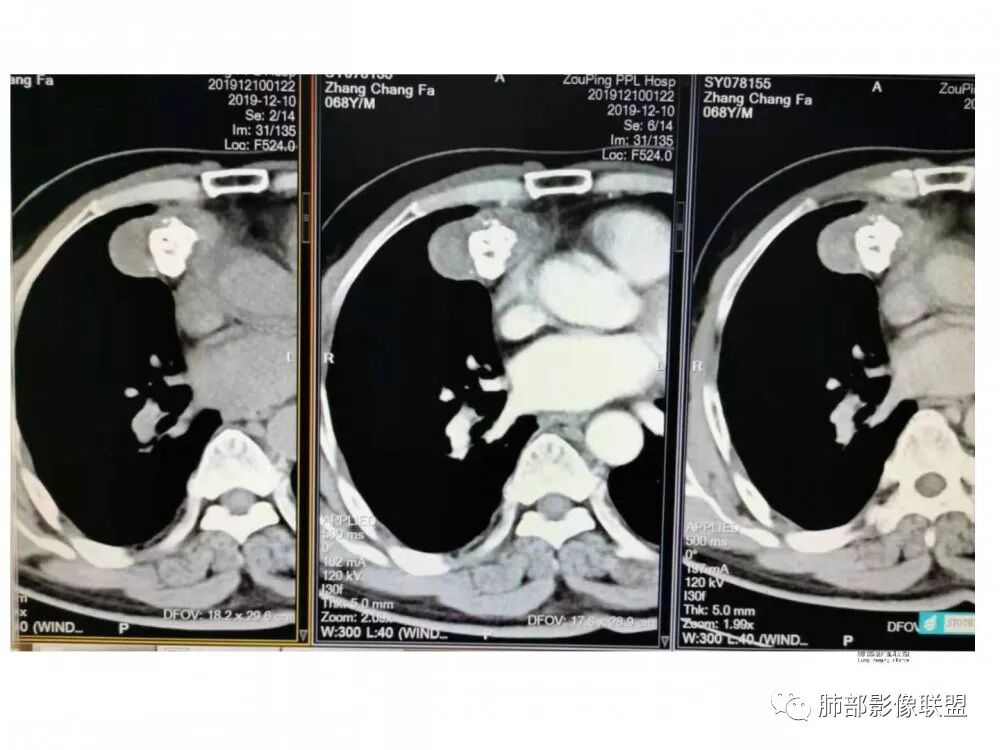

滴水海:胸膜掀起定位纵隔,明显分叶,大块钙化,中度不均强化,从钙化特点入手,可见于畸胎瘤,巨淋,胸腺瘤,类癌,结核球,软骨瘤,可能性依次递减。巨淋强化不是太高,周围无增粗血管和淋巴结。如此明显分叶,若是胸腺瘤则是B3型及以上了,但其大块钙化似乎少见,明显坏死也没看到,对周围也未见明显侵犯。上二者少见表现或许有故次之。类癌若位于纵隔一般胸腺类癌,其钙化特点见得少,增粗迂曲血管多见,不典型,若是肺内类癌则可能性增大。结核球强化又太高。软骨瘤见的极少,曾见过一例心包软骨肉/瘤,罕见

尘缘:

右前纵隔不规则肿块,分叶状,内见斑块状钙化,肺组织受压内移,胸膜抛起,胸膜下纵隔脂肪间隙不清,增强后轻度强化,右侧内乳动脉无明显增粗,定位于纵隔内,定性:畸胎瘤与胸腺瘤鉴别,形态不规则,分叶,钙化明显,右侧内乳动脉不粗,畸胎瘤可能>胸腺瘤。

冥冥之中:纵隔来源的占位,胸腺瘤跟畸胎瘤的鉴别

年龄上,胸腺瘤大于畸胎瘤